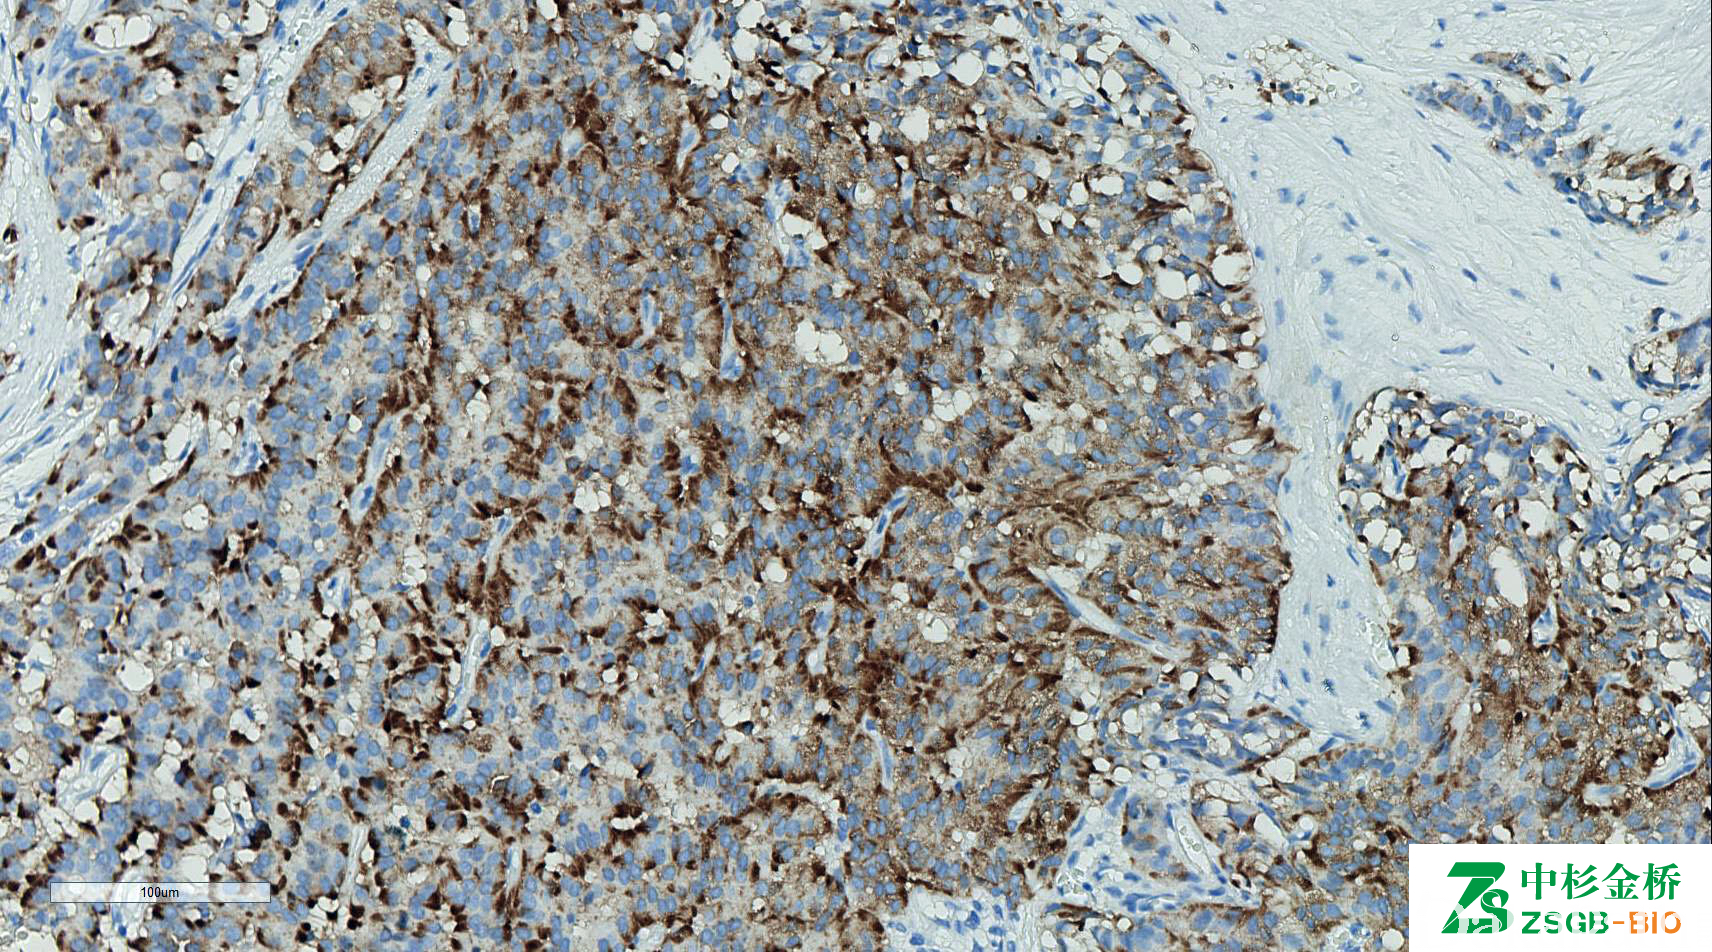

Synaptophysin

别名: Syn;突触素

神经内分泌标记之一,与神经内分泌细胞反应。

信号定位: 胞质